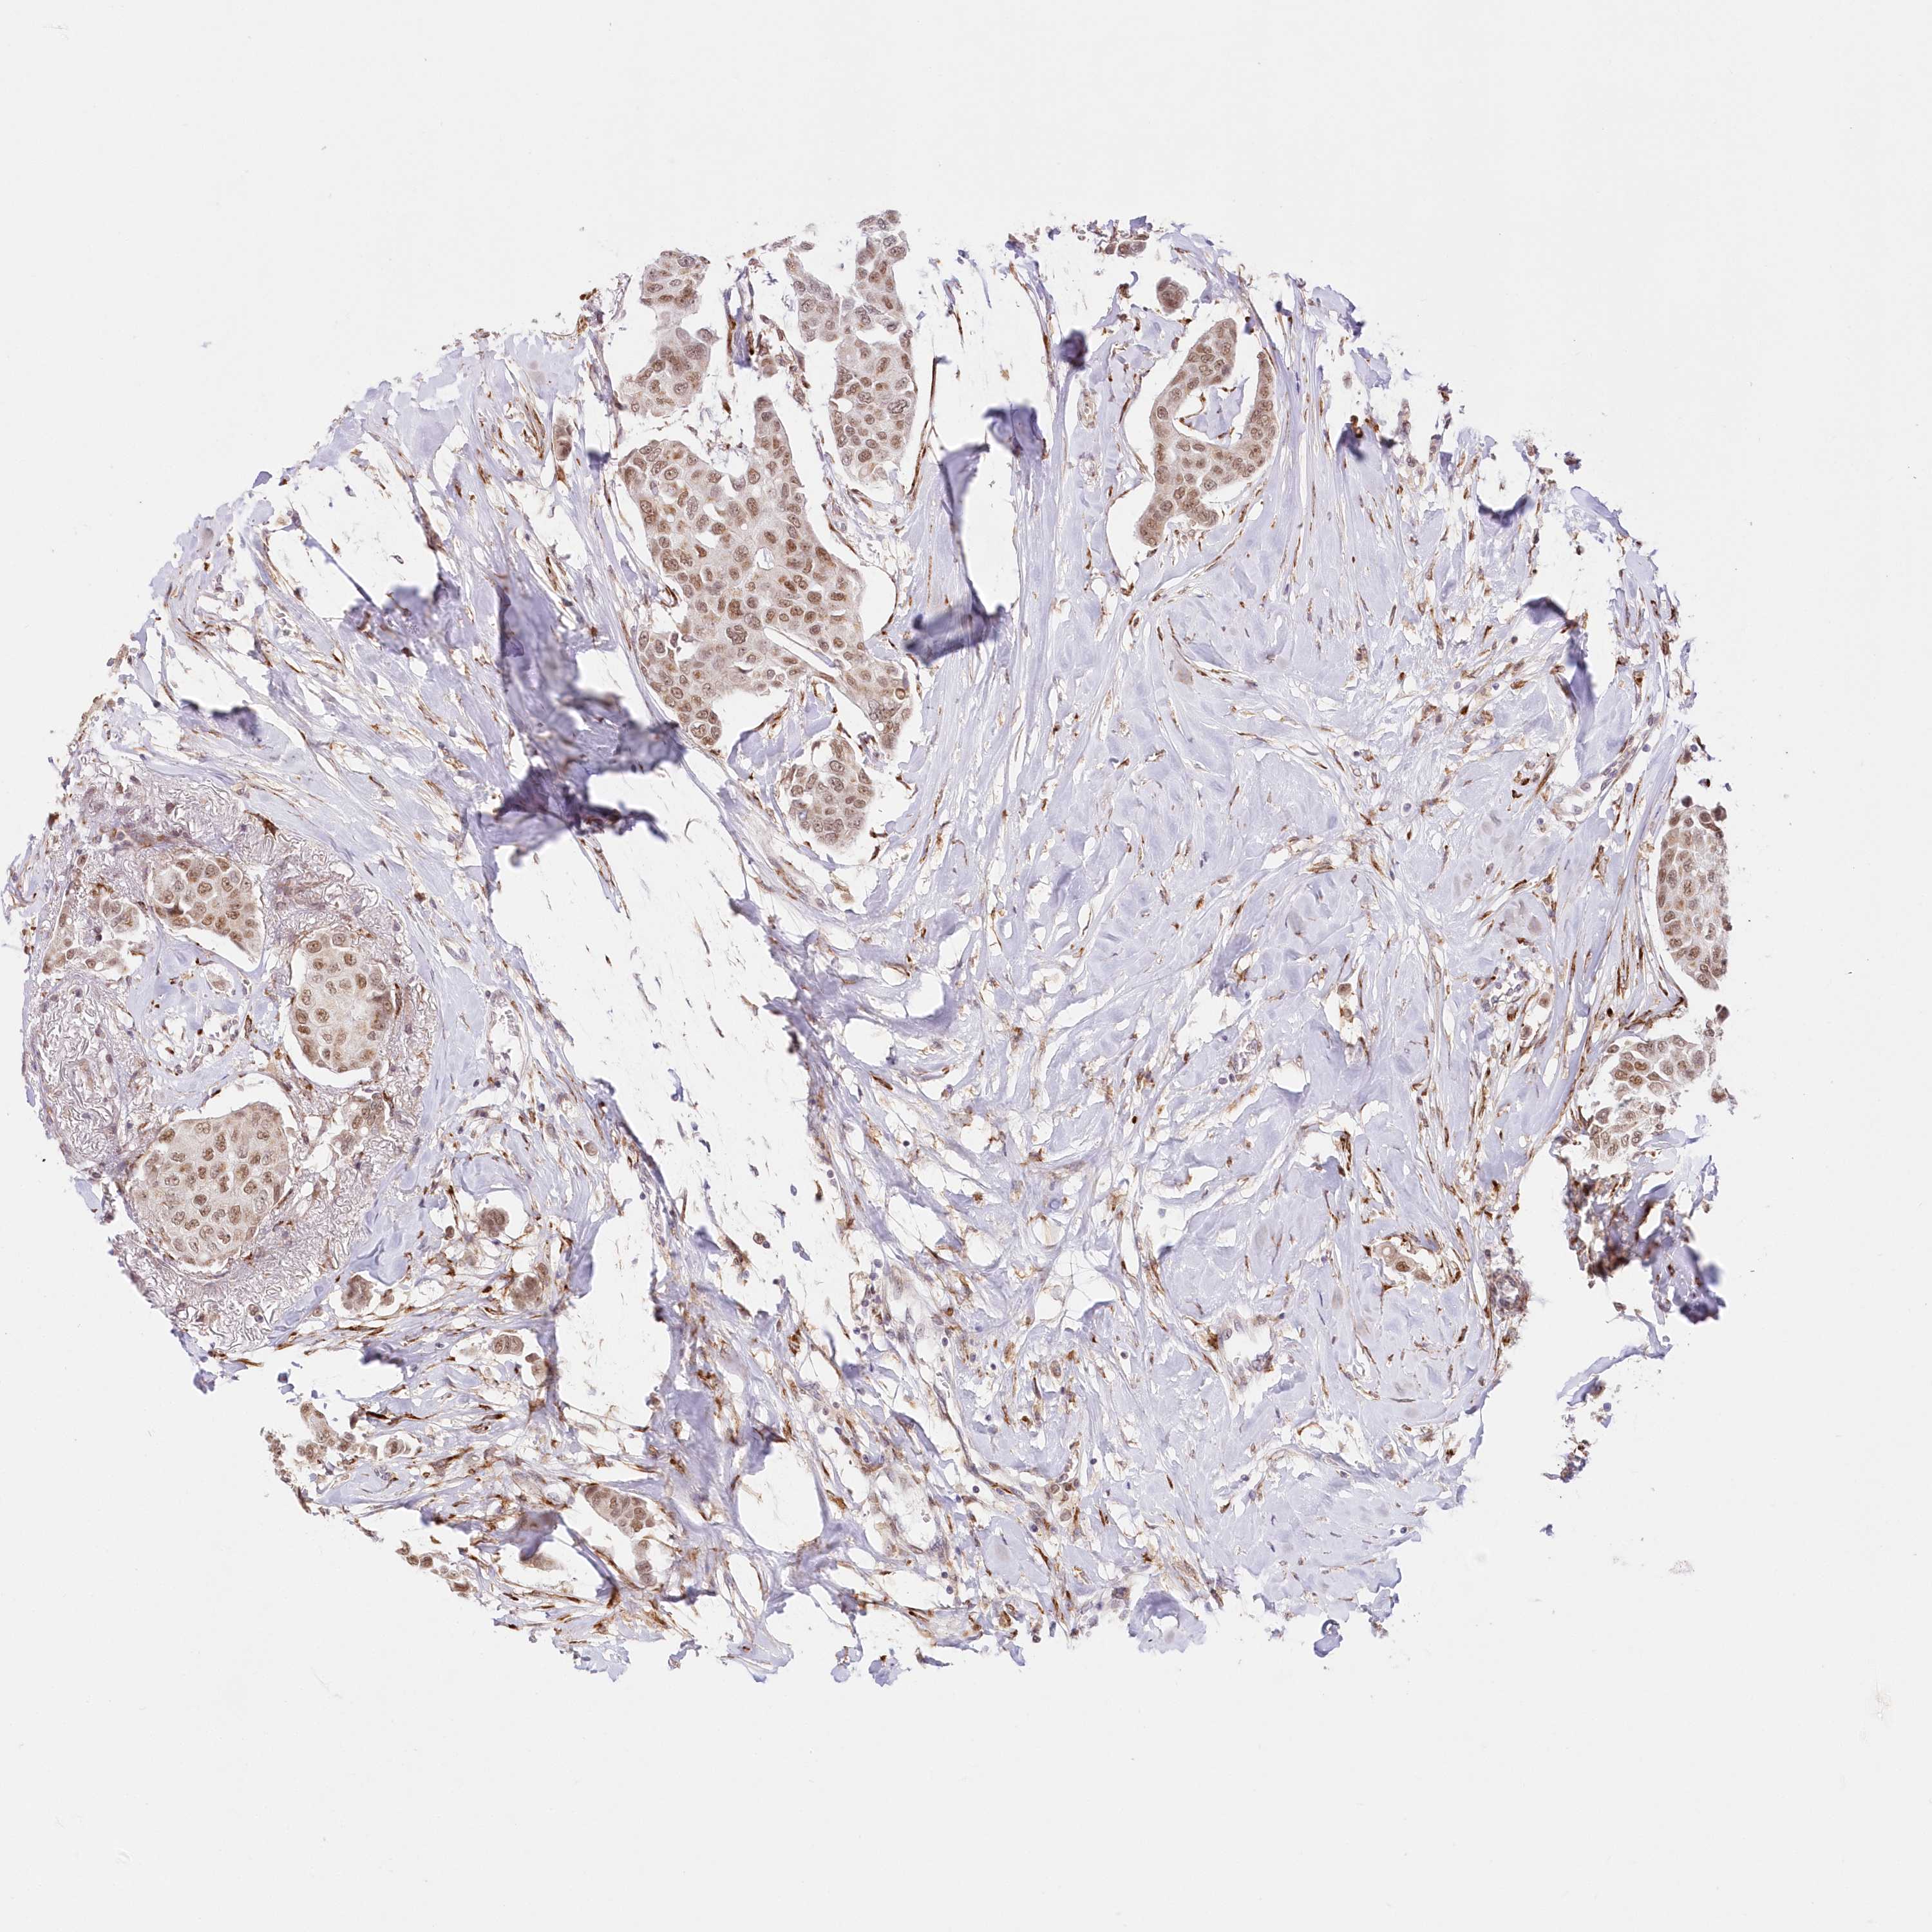

CANCER BREAST CANCER Show tissue menu

BRCA TCGA BRCA VALIDATION PROTEIN EXPRESSION

Breast cancer

Human cancer